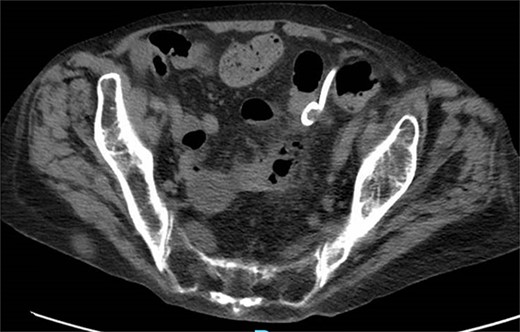

One month prior, the patient was admitted for complicated perforated sigmoid diverticulitis. Treatment included piperacillin-tazobactam (Zosyn), bowel rest, and fluid resuscitation. On hospital Day 6, her condition worsened with increased nausea, vomiting, and an elevated WBC count of 15. CT imaging revealed a 4.8 × 4.4 × 4.0 cm diverticular abscess, leading to CT-guided percutaneous drainage by interventional radiology (Figs 4–7). Cultures grew Citrobacter sedlakii and Enterococcus faecium vancomycin resistant Enteroccus (VRE), and treatment was adjusted to include Bactrim, followed by daptomycin and levofloxacin. The abscess resolved after 3 weeks, and the drain was removed before discharge. The patient was instructed to follow up with her surgeon and undergo a 6-week interval colonoscopy.

CT showing resolution of abscess with IR pigtail drain in place.